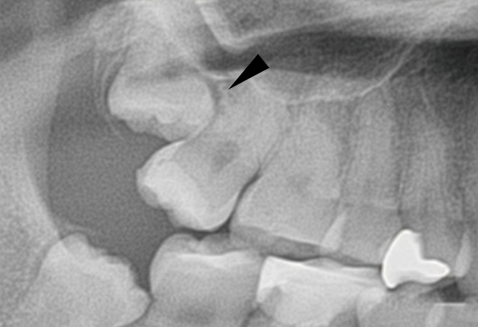

同じ症例をレントゲン写真で見たところです。親知らずが横倒しに生えていて、周りの骨を溶かしてしまっています。

親知らずが横(水平)に生えている写真です。隣の歯との隙間は歯磨きすることは出来ません。放っておくと、次の写真の様になります。

左の親知らずは、大事な一本前の歯を虫歯にし、さらに周りの骨を溶かしています。こうなってからでは遅すぎてしまいます。